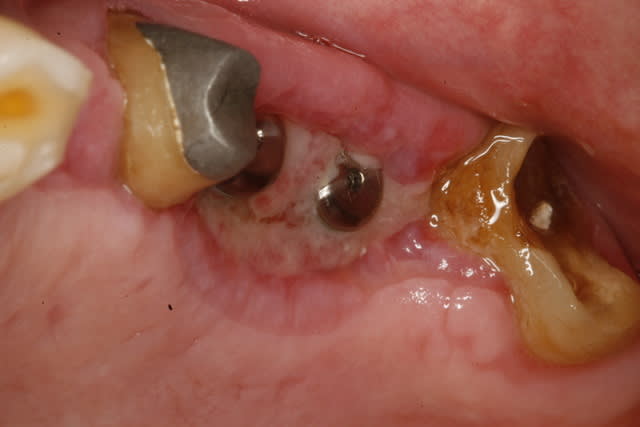

necrose du lambeau coté palatin les photos à 18 J

comme promis les voilà!!!!

_MG_1013_fqco0d.jpg

_MG_1015_dmvdwt.jpg